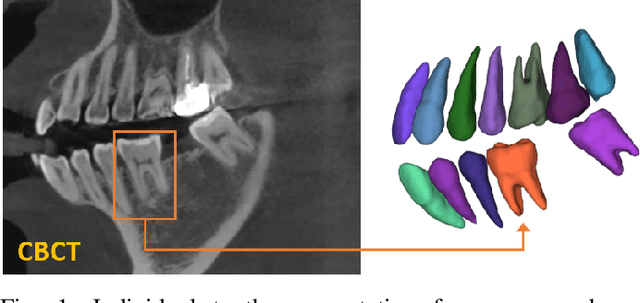

Abstract:Individual tooth segmentation from cone beam computed tomography (CBCT) images is an essential prerequisite for an anatomical understanding of orthodontic structures in several applications, such as tooth reformation planning and implant guide simulations. However, the presence of severe metal artifacts in CBCT images hinders the accurate segmentation of each individual tooth. In this study, we propose a neural network for pixel-wise labeling to exploit an instance segmentation framework that is robust to metal artifacts. Our method comprises of three steps: 1) image cropping and realignment by pose regressions, 2) metal-robust individual tooth detection, and 3) segmentation. We first extract the alignment information of the patient by pose regression neural networks to attain a volume-of-interest (VOI) region and realign the input image, which reduces the inter-overlapping area between tooth bounding boxes. Then, individual tooth regions are localized within a VOI realigned image using a convolutional detector. We improved the accuracy of the detector by employing non-maximum suppression and multiclass classification metrics in the region proposal network. Finally, we apply a convolutional neural network (CNN) to perform individual tooth segmentation by converting the pixel-wise labeling task to a distance regression task. Metal-intensive image augmentation is also employed for a robust segmentation of metal artifacts. The result shows that our proposed method outperforms other state-of-the-art methods, especially for teeth with metal artifacts. The primary significance of the proposed method is two-fold: 1) an introduction of pose-aware VOI realignment followed by a robust tooth detection and 2) a metal-robust CNN framework for accurate tooth segmentation.